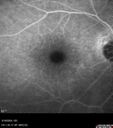

Central Retinal Vein Occlusion with cilioretinal artery occlusion72 views63 year old female who lost vision in the left eye 2 days ago. She was in the emergency room and had a lot of tests done which were all reportedly normal. The right eye is OK.

VA OD: Dcc20/25 NccJ2

VA OS: Dcc20/200-1 PHNI Ncc20/400-1

IOP: TP: OD:11 OS:12